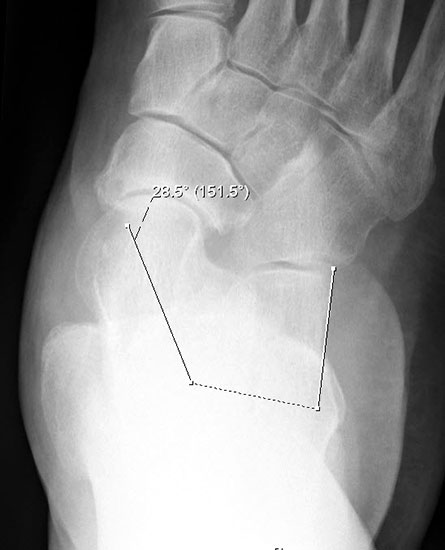

Auf der seitlichen, stehenden Aufnahme des Fußes wird ebenfalls der laterale Talo-Metatarsale I Winkel (Abb. 6 d) gemessen und so das kollabierte mediale Längsgewölbe dokumentiert. Auch hier gilt ein Talo-Metatarsale I Winkel von > 5° (nach plantar konvex) als pathologisch 21. Der Kollaps findet dabei meist im Talonaviculargelenk, seltener in der Naviculocuneiform-Gelenkreihe statt. Instabilität und Arthrose im 1. TMT sollten ausgeschlossen oder bei der Operationsplanung mit einbezogen werden. Weitere wichtige radiologische Messungen zur Beurteilung der Planovalgus-Statik und Progression der Deformität sind der laterale talo-calcaneare Winkel (Abb. 6 e) und der Abstand des Os cuneiforme-Unterrandes zum Untergrund (Abb. 6 f, Cuneiform height, 22. Eine anteriore Translation des Talus auf dem Kalkaneus findet man sowohl auf der ap, als auch auf der seitlichen Aufnahme des Fuβes mit Aufhebung der Cima-Linie.

Talo-Metatarsale I Winkel >5°: abgeflachtes Längsgewölbe (Abb. 6d)

Talo-calcanearer Winkel (Abb. 6 e)

„Cuneiforme height“ (Abb. 6f)